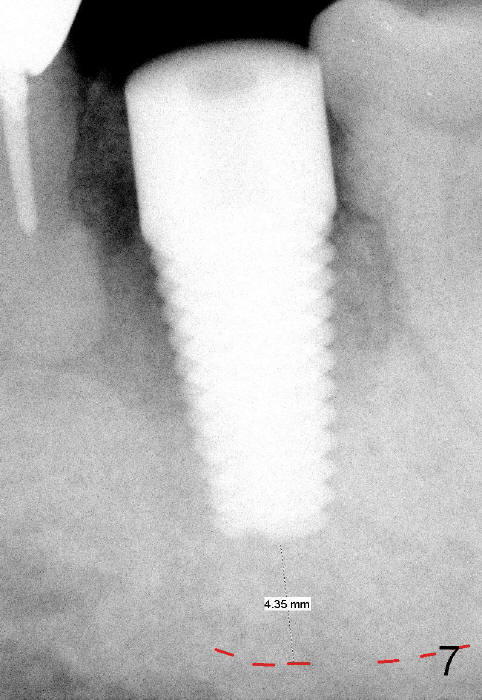

When a 7x17mm tap is inserted, it is stable. There is distance to the inferior alveolar nerve (Fig.6: dashed line).

Prior to implant placement (Fig.7,9: 7x17 mm with insertion torque 40 Ncm), a mixture of autogenous bone (Fig.8 red particles) and demineralized cortical allograft (white granules) is packed against defective socket walls, particularly apically. It leaves a space in the middle of the socket for implant insertion later on. In this case, the buccal wall around the apex, corresponding to the fistula (Fig.9 >) is severely destroyed, whereas the crestal portion is more or less intact. Three months later, the implant appears yet to osteointegrate (Fig.10), while the fistula disappears (Fig.11). The large implant does not look too overengineered over the alveolus (Fig.12 (lingual view). In fact, the implant has mild mobility. How to fix it?